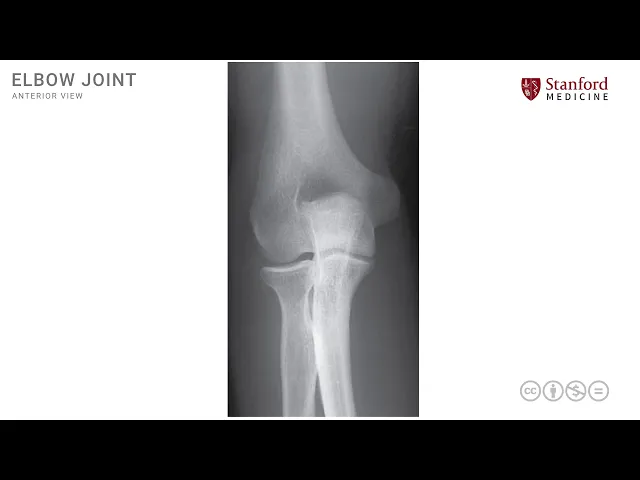

here which accommodates the coronoid process in full flexion similarly we have a radial fossa which is seen over here to accommodate the radial head in full flexion these are some of the key structures in the arab elbow region let's now look at a simple x-ray this is a plane ap x-ray in anteroposterior x-ray of the right elbow joint and we can see some of the same structures again this is the humerus which is the distal end of this bone we can also see the ulna and the radius more distally over here this is the radius

on this side and this is the ulna on this side and these three bones participate in the formation of the elbow joint which is a hinge joint the coronoid process can be seen over here and is outlined here in yellow orange color similarly the radial head is seen over here and is outlined in reddish orangish color over here these are two key structures that articulate with the distal end of the humerus to form the elbow joint or as a as known as a hinge joint the lateral epicondyle and the medial epicondyle are also seen over

here on the distal end of the humerus and over here on the lateral side of the distal end of the humerus the olecranon is seen over here which is a very interesting structure seen on the posterior side and requires a posterior vantage point view we can see it in an x-ray because the radiation goes through and through and it is overlapping with the condylar area of the humerus we will see this more clearly in a lateral view of the elbow joint in the olecranon fossa is the area on the distal humerus that accommodates this electron